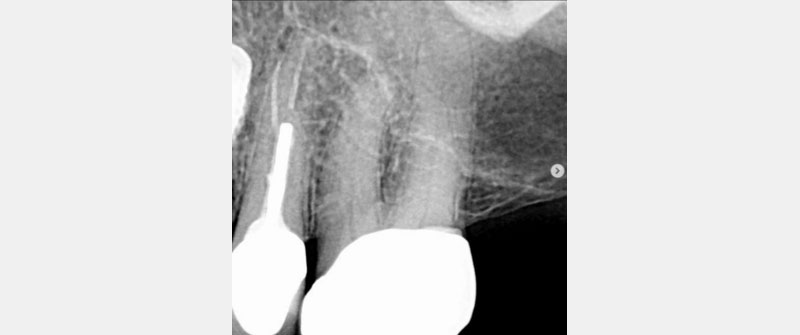

A recent PA, with the BW you might already have, will provide essential information about that tooth. Are the pulp chambers uniform and evident? Can you see the pulp chambers? Are they grey? Or are they sandwiched and shrunken (aka calcifying or calcified)?

Can you cold test the tooth? If calcified, it might not respond to cold, so how do you assess? Is the cold response the same intensity as all the other teeth? Can you percuss the tooth? Is it different in how it feels versus the adjacent teeth or virgin nearby teeth (if applicable)? If not, can you suggest an endodontic consultation?

As a side note, it usually takes approximately three months for radiographic changes of pulpal necrosis to become evident with a periapical lucency. Please remember these lucencies aren’t always evident.

In Figs. 7–9, each patient was asymptomatic, but clearly all had medium- to large-sized restorations.